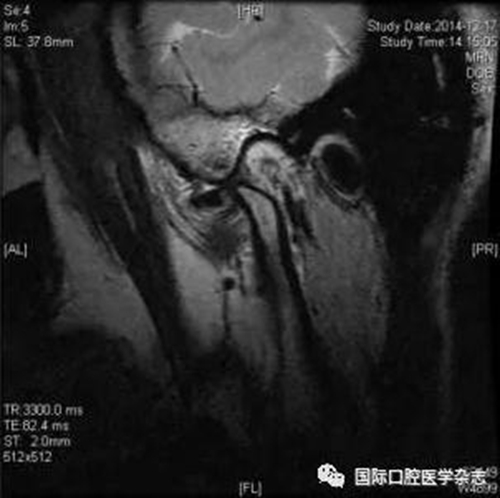

(2)不可復(fù)性關(guān)節(jié)盤前移位(圖1):多見于青壯年,往往與社會(huì)心理因素、牙合關(guān)系異常、代謝因素、偏側(cè)咀嚼、夜磨牙及不良習(xí)慣等因素相關(guān)。張口運(yùn)動(dòng)時(shí),受髁突擠壓變形的關(guān)節(jié)盤不能復(fù)位;臨床有典型的關(guān)節(jié)彈響病史,進(jìn)而彈響消失,出現(xiàn)開口受限,開口時(shí)下頜偏患側(cè)及關(guān)節(jié)區(qū)疼痛。測(cè)量被動(dòng)開口度時(shí),開口度不能增大。輔助檢查中,錐形束CT顯示關(guān)節(jié)前間隙增寬,造影片或核磁共振成像(magnetic resonance imaging,MRI)顯示不可復(fù)性關(guān)節(jié)盤前移位。

圖 1 不可復(fù)性關(guān)節(jié)盤前移位